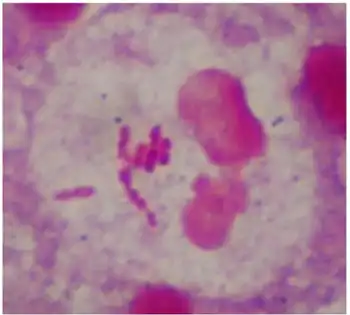

Gram-negative bacteria are found in virtually all environments on Earth that support life. The gram-negative bacteria include the model organism Escherichia coli, as well as many pathogenic bacteria, such as Pseudomonas aeruginosa, Chlamydia trachomatis, and Yersinia pestis. They are a significant medical challenge as their outer membrane protects them from many antibiotics (including penicillin), detergents that would normally damage the inner cell membrane, and lysozyme, an antimicrobial enzyme produced by animals that forms part of the innate immune system. Additionally, the outer leaflet of this membrane comprises a complex lipopolysaccharide (LPS) whose lipid A component can cause a toxic reaction when bacteria are lysed by immune cells. This toxic reaction may lead to low blood pressure, respiratory failure, reduced oxygen delivery, and lactic acidosis – manifestations of septic shock.[2]

Medically relevant gram-negative cocci include the four types that cause a sexually transmitted disease (Neisseria gonorrhoeae), a meningitis (Neisseria meningitidis), and respiratory symptoms (Moraxella catarrhalis, Haemophilus influenzae).

One of the several unique characteristics of gram-negative bacteria is the structure of the bacterial outer membrane. The outer leaflet of this membrane contains lipopolysaccharide (LPS), whose lipid A portion acts as an endotoxin.[1] If gram-negative bacteria enter the circulatory system, LPS can trigger an innate immune response, activating the immune system and producing cytokines (hormonal regulators). This leads to inflammation and can cause a toxic reaction, resulting in fever, an increased respiratory rate, and low blood pressure. That is why some infections with gram-negative bacteria can lead to life-threatening septic shock.[2]

The outer membrane protects the bacteria from several antibiotics, dyes, and detergents that would normally damage either the inner membrane or the cell wall (made of peptidoglycan). The outer membrane provides these bacteria with resistance to lysozyme and penicillin. The periplasmic space (space between the two cell membranes) also contains enzymes which break down or modify antibiotics. Drugs commonly used to treat gram negative infections include amino, carboxy and ureido penicillins (ampicillin, amoxicillin, pipercillin, ticarcillin) these drugs may be combined with beta-lactamase inhibitors to combat the presence of enzymes that can digest these drugs (known as beta-lactamases) in the peri-plasmic space. Other classes of drugs that have gram negative spectrum include cephalosporins, monobactams (aztreonam), aminoglycosides, quinolones, macrolides, chloramphenicol, folate antagonists, and carbapenems.[15]